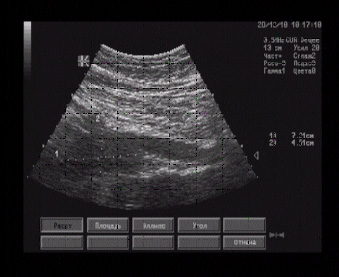

При сканировании по срединной линии в подчревной области в проекции брюшного отдела аорты лоцируется образование 85 х 45 мм, имеющее неправильную форму, бугристую поверхность, нечеткие границы, однородное гипоэхогенное строение.

Эхографические признаки гипоэхогенного образования в проекции брюшного отдела аорты, напоминающего конгломерат гиперплазированных лимфатических узлов. Эхоструктурных изменений печени не выявлено.